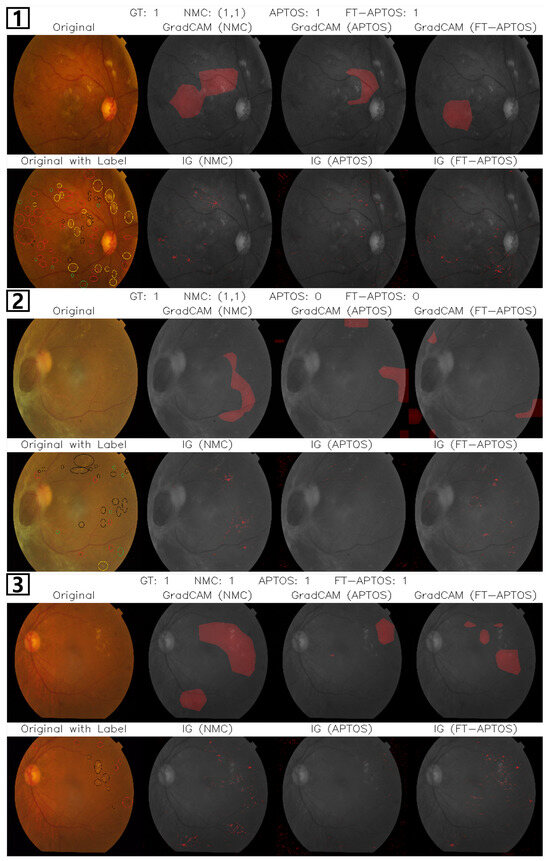

We employed two widely used explainability techniques—GradCAM [46] and IG [47]—to interpret model decision-making and assess its sensitivity to clinically meaningful lesion features. These methods were applied to models trained independently on the APTOS and NMC datasets, as well as to the FT-APTOS model, which was pretrained on NMC and fine-tuned on APTOS. To highlight the most salient activation patterns, only the top 30% of each model’s response map was visualized.

For objective comparison, expert ophthalmologists manually annotated the APTOS fundus images at the pixel level. Each lesion type was marked using distinct colors: hard exudates (black), hemorrhages (red), microaneurysms (green), and cotton wool spots (yellow). These annotations provided reference boundaries to evaluate whether the models’ attention aligned with known diagnostic markers.

Figure 5 presents visualization results comparing models trained on APTOS, NMC, and a model pretrained on NMC and fine-tuned on APTOS (FT-APTOS) across different DR severity classes. In the first example of Class 3 (Severe NPDR), which was correctly classified by all models, the NMC-trained model precisely highlighted hemorrhages and microaneurysms—both key diagnostic markers of Severe NPDR—in the IG maps. In contrast, the APTOS-trained model showed broader attention dispersed across background regions, indicating weaker localization of relevant lesions. The FT-APTOS model exhibited sharper focus in IG visualizations, aligning more closely with annotated lesion clusters. These results suggest that lesion-centered pretraining enhances spatial selectivity toward clinically meaningful features, thereby improving severity classification accuracy.

In the second case of Class 3, only the NMC-trained model made an accurate prediction, clearly reflected in the visualizations. Visualizations from the APTOS-trained model exhibited weak and spatially diffuse activation across background regions, failing to capture key pathological features. The FT-APTOS model showed improved attention to detail in lesion location in the IG results. However, the GradCAM visualizations revealed weak activation in these regions.

In our third example featuring Class 2 (Moderate NPDR), all three models correctly classified the image. However, the Integrated Gradients visualizations reveal a significant improvement in attention focusing with the FT-APTOS model. While the NMC-trained model attends to non-diagnostic lesions and the APTOS-trained model focuses primarily on several lesions, the FT-APTOS model demonstrates an enhanced ability to prioritize clinically significant regions while suppressing attention to less important areas. This suggests that the combined knowledge from both datasets enables the model to more effectively distinguish between diagnostically relevant and irrelevant features, resulting in more precise focus on the hemorrhagic lesions that define Moderate NPDR.

Overall, IG results show that the NMC-trained model focuses sharply on lesions like hemorrhages and microaneurysms, closely matching expert annotations. The APTOS-trained model displays broader, less specific attention as it concentrates primarily on severity criteria rather than precise lesion identification, resulting in insufficient feature focusing for its classification decisions. When both approaches are combined in the FT-APTOS model, we observe more refined localization, with the lesion-specific knowledge from NMC complementing the severity-based approach of APTOS to support more informed model decision-making. This suggests that lesion-focused pretraining improves clinical feature alignment and classification accuracy by enhancing the model’s ability to identify the specific pathological features that drive severity assessment. While these findings demonstrate the benefits of combining approaches, challenges remain in fully bridging lesion detection and severity classification, suggesting opportunities for future research using mechanisms like multi-task learning or hierarchical supervision.